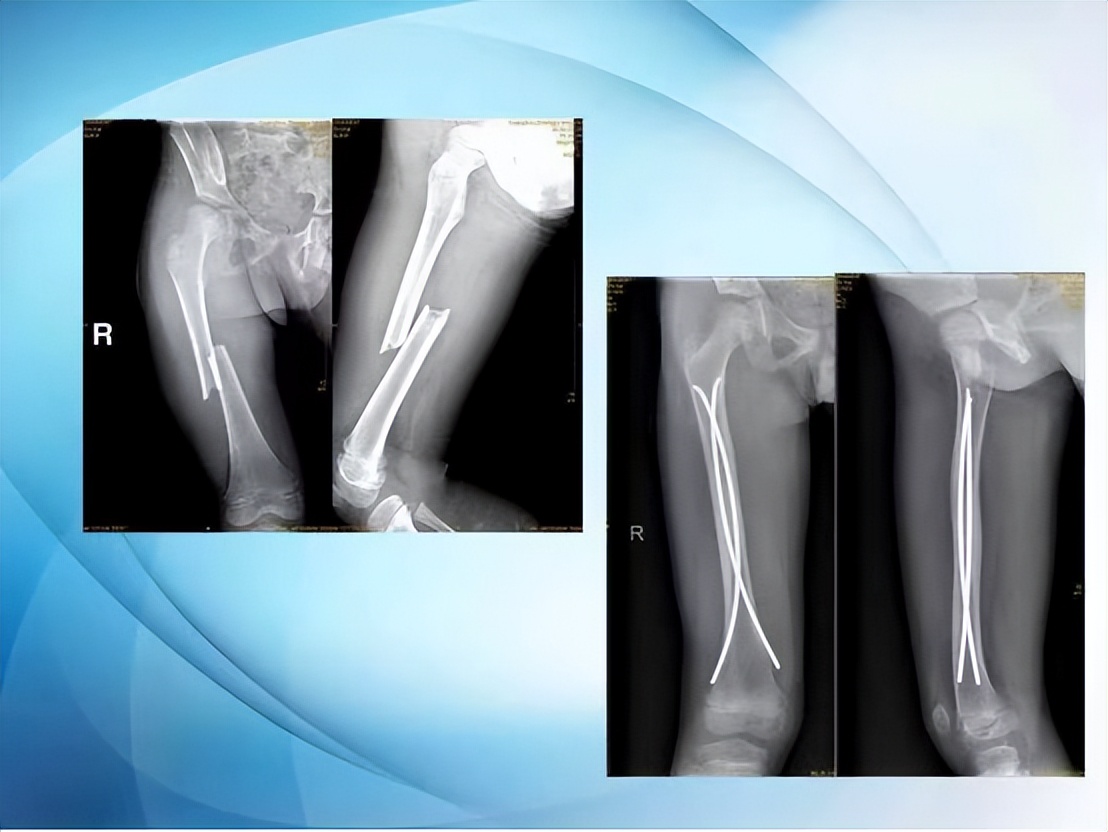

小儿手术治疗骨科疾病主张无创、微创治疗。微创手术的优势是手术时间短、切口小、患儿痛苦少、术中损伤小、术后恢复快。在微创手术的大趋势下,小儿骨科不断开展新技术新疗法,如:闭合复位治疗儿童肱骨髁上骨折、闭合复位弹性髓内钉内固定术治疗儿童长骨干骨折等,解决了传统手术切口长、出血多、损伤大、术后恢复时间长的弊端。

弹性髓内钉治疗儿童的长骨骨折,其特点是创伤小,进行微创操作不影响孩子的骨骼发育,对于骨折的愈合以及孩子以后的骨骼发育影响小。比较常见的骨折,比如胫骨骨折、股骨干骨折、尺桡骨骨折,对于这类长管状骨骨折,弹性髓内钉可以在骨折的一端进行微创操作:非常小的皮肤切口,一般在1厘米左右,通过c型臂透视下打入弹性髓内钉,弹性髓内钉在骨髓腔内走形,起到恢复骨折断端的力线、维持骨折断端的稳定而不伤及骨垢的作用。